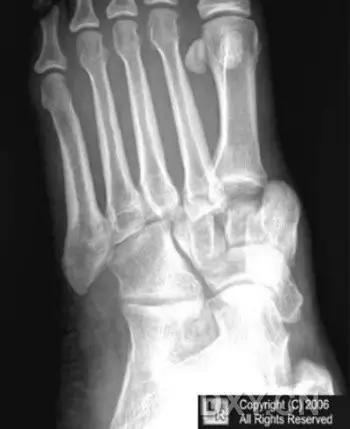

14.第五跖骨骨折

第五跖骨基底部骨折的不同类型:Stress 骨折;Jones 骨折:第五跖骨基底部以远 1 英寸内的骨折称为 Jones 骨折; Avulsion 骨折。

(来源:Radiopaedia)

Stress 骨折(来源:OrthoInfo-AAOS)

Jones 骨折正位片(来源:Radiopaedia)

Jones 骨折斜位片(来源:Radiopaedia)